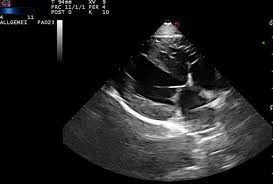

A veces una herramienta valiosa, a veces imprescindible.

La ecografía es un procedimiento con un grán valor en veterinaría, haciéndose imprescindible para poder llegar a ciertos diagnósticos así como para valorar la gravedad y evolución de ciertas patologías.

En nuestro centro disponemos de ecógrafo propio, con lo que podemos realizar esta prueba en el momento  y para casos especiales o patologías complejas, contamos con un sevicio especializado de ecografistas que, previa cita, realizaran esta prueba a su mascota siempre bajo recomendación veterinaria.